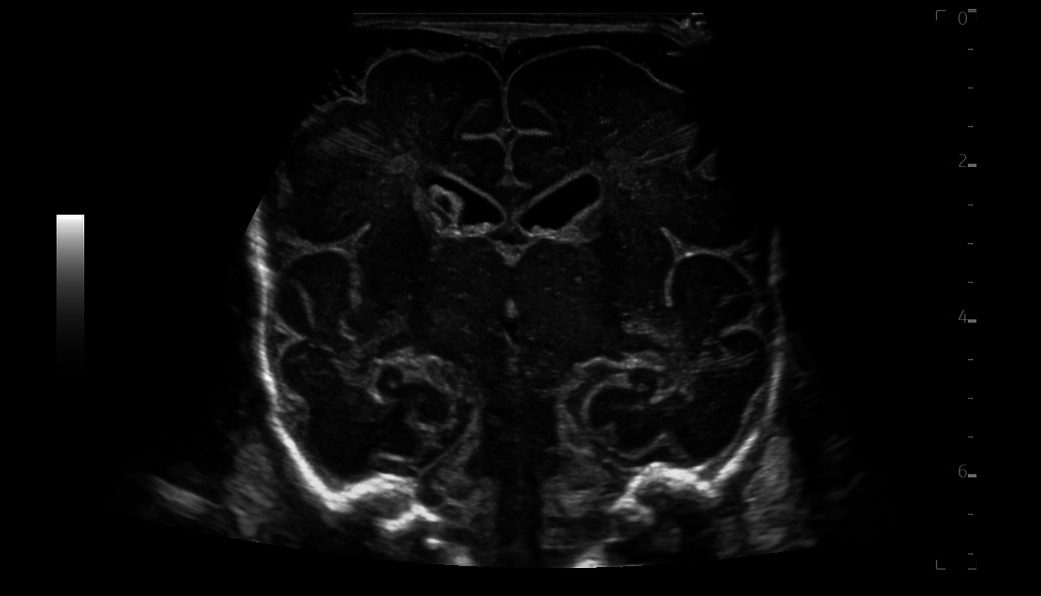

Gain the confidence with extraordinary image quality and non-invasive robust imaging tools

LOGIQ Ultrasound, with cSound™ Imageformer, enables delivering images of incredible uniformity from near to far field. Thereʼs no need to manually adjust the focus - the information you need is there, instantly.

B-Flow imaging - non-Doppler technique - enables direct, real-time visualization of blood flow echoes with no vessel wall overlap to obscure details

2D Shear Wave Elastography enables non-invasive 2D quantitative assessment of tissue stiffness

Contrast-Enhanced Imaging (CEUS) optimizes the balance between penetration and resolution for improved contrast sensitivity